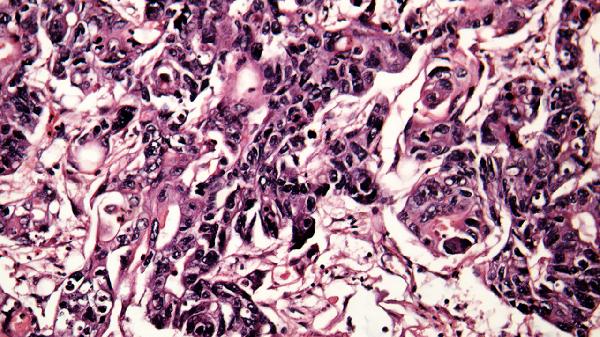

4、下肢静脉血栓:

肺气肿患者因活动量减少、血液高凝状态易形成深静脉血栓,表现为单侧腿部突发肿胀剧痛,皮肤温度升高。需立即进行血管超声检查,确诊后需使用低分子肝素等抗凝药物,严重时需放置下腔静脉滤器。